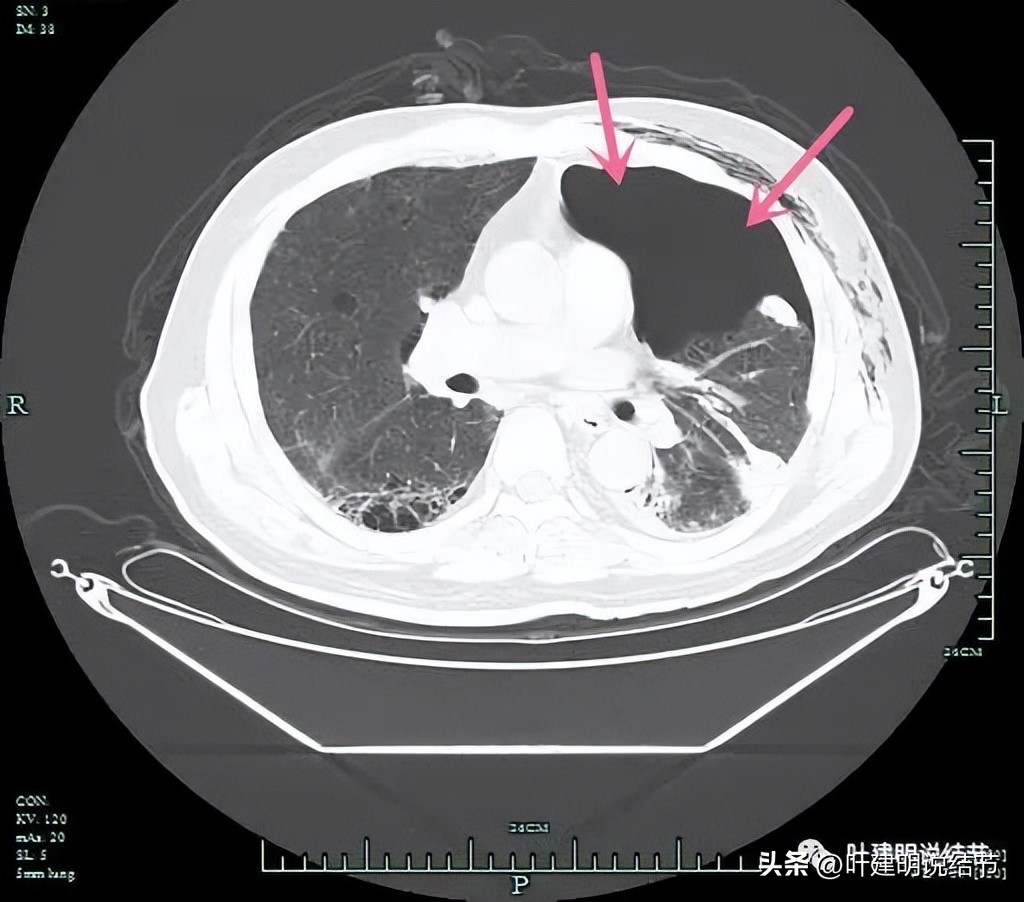

穿刺致气胸。

穿刺未能确诊。